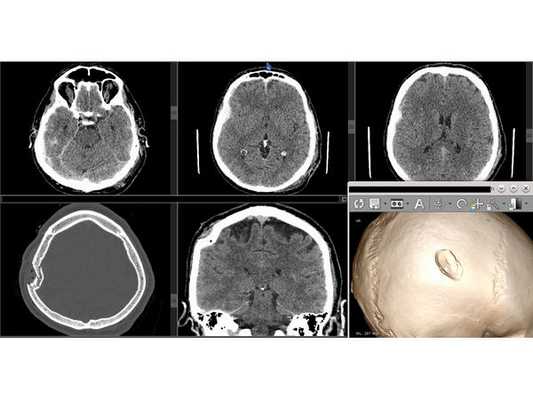

На компьютерной томографии выявлена травматическая патология черепа и головного мозга. От предложенной госпитализации пациент отказался. Повторно доставлен в больницу бригадой скорой медицинской помощи по направлению из участковой больницы по месту жительства.

- Оскольчатый вдавленный перелом правой теменной кости.

- Линейный перелом затылочной кости.

- Перелом клеток решётчатого лабиринта справа с признаками эмфиземы (скопления воздуха) тканей правой орбиты.

- Гемосинус (скопление крови в придаточной пазухе носа) клеток решётчатого лабиринта справа.

На контрольной КТ головного мозга в послеоперационном периоде видна положительная динамика: состояние после краниотомии, репозиции вдавленных фрагментов теменной кости, удаления субдуральной гематомы, регресса дислокации срединных структур стабильное.